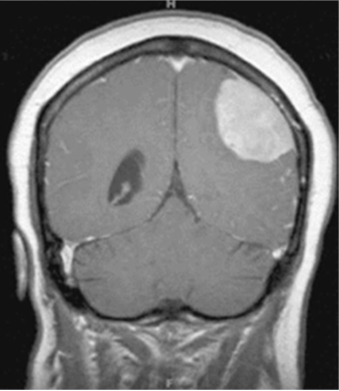

Question: A 58-year-old man presents with a 2-months history of gradually progressive right hemiparesis. A contrast-enhanced magnetic resonance image of the brain is shown here. What is the most likely diagnosis for the lesion shown?

Explaination: The image demonstrates a meningioma arising from the left parietal convexity. The most telling characteristics of the image include the intense bright, homogeneous enhancement pattern, the extra-parenchymal location, and the dural tail at the superior margin.